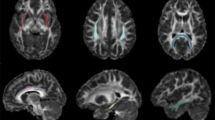

Ketamine is an N-methyl-D-aspartate (NMDA) receptor antagonist that has been found to induce schizophrenia-type symptoms in humans and is a potent and fast-acting antidepressant. It is also a relatively widespread drug of abuse, particularly in China and the UK. Acute administration has been well characterized, but the effect of extended periods of ketamine use—on brain structure in humans—remains poorly understood. We measured indices of white matter microstructural integrity and connectivity in the brain of 16 ketamine users and 16 poly-drug-using controls, and we used probabilistic tractography to quantify changes in corticosubcortical connectivity associated with ketamine use. We found a reduction in the axial diffusivity profile of white matter in a right hemisphere network of white matter regions in ketamine users compared with controls. Within the ketamine-user group, we found a significant positive association between the connectivity profile between the caudate nucleus and the lateral prefrontal cortex and dissociative experiences. These findings suggest that chronic ketamine use may be associated with widespread disruption of white matter integrity, and white matter pathways between subcortical and prefrontal cortical areas may in part predict individual differences in dissociative experiences due to ketamine use.